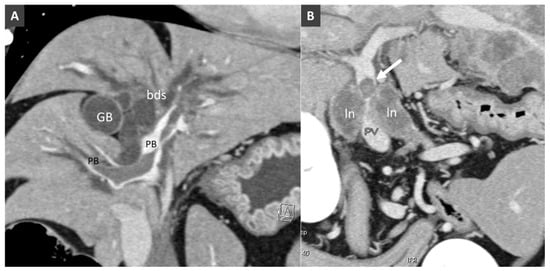

3.8. Porto-Portal Collaterals or Cavernous Transformation of the Portal Vein